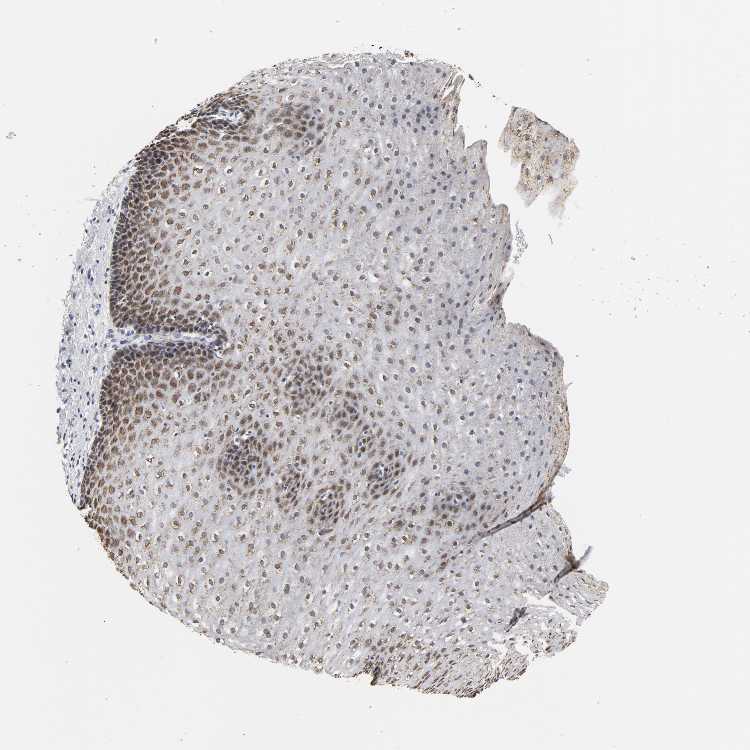

Antibody HPA004820

Squamous epithelial cells Medium